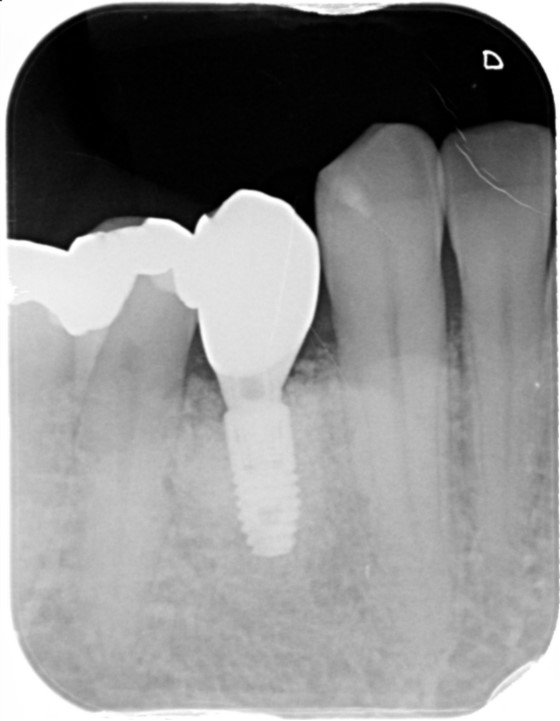

30代 男性

当院に歯の痛み、腫れを主訴にお見えになりました。マイクロスコープで確認したところ歯が複雑に破折しており保存は難しい状態でした。そのため、しっかりとご説明させていただき抜歯の選択を行いました。

インプラントと入れ歯とブリッジの選択をご説明し、隣の歯が健全な状態であり負担をかけたくないためにインプラント治療を選択頂きました。治療は3か月にて終了しました。術後2年ですが問題なくなんでも噛めるとおっしゃていただいております。

治療部位 | 左下6部 |

費用 | 450000円 |

治療期間 | 3か月 |